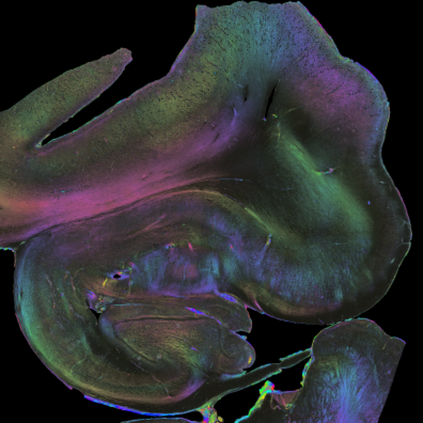

Understanding the cortical organization of the human brain requires interpretable descriptors for distinct structural and functional imaging data. 3D polarized light imaging (3D-PLI) is an imaging modality for visualizing fiber architecture in postmortem brains with high resolution that also captures the presence of cell bodies, for example, to identify hippocampal subfields. The rich texture in 3D-PLI images, however, makes this modality particularly difficult to analyze and best practices for characterizing architectonic patterns still need to be established. In this work, we demonstrate a novel method to analyze the regional organization of the human hippocampus in 3D-PLI by combining recent advances in unfolding methods with deep texture features obtained using a self-supervised contrastive learning approach. We identify clusters in the representations that correspond well with classical descriptions of hippocampal subfields, lending validity to the developed methodology.